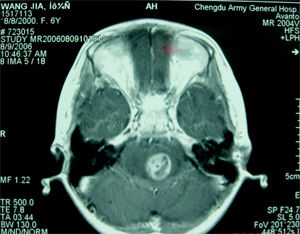

血管網狀細胞瘤病理圖腫瘤肉眼觀察可為囊性或囊實性,也有實質腫瘤囊性變者。腫瘤境界清,紫紅色,質較韌,直徑大小不一,同腦組織關係密切切面呈暗紫色。鄰近腦膜可有血管擴張。可有棕黃色的含鐵血黃素沉積於囊壁和腫瘤結節內。腫瘤呈囊性者占80%,特別是小腦血管囊性變者更多見。囊內含黃色或黃褐色液體,多在10~100ml之間。囊液蛋白含量較高,易凝固成膠凍樣。測定囊液蛋白質含量每100ml可達3~4g,系腫瘤滲出液腫瘤囊腔內壁光滑,有一富於血管的瘤結節,1/4腫瘤為實質性血運極為豐富如血竇樣紅色瘤結節突入囊內約2cm大小,但有些瘤結節小於1cm,有些甚至隱藏於囊壁內,不易被發現實體腫瘤多較大個別的直徑可達10cm,呈紫色鮮紅色、黃色質軟,血運豐富易出血,與周圍腦組織分界清楚。大多數病例為單發性腫瘤少數病例可有多個腫瘤分布於腦的不同部位。

顱內血管網狀細胞瘤絕大部分發生在幕下,成人有小腦腫瘤症狀及顱內壓增高症狀者,應考慮血管網狀細胞瘤的可能,尤其有下述表現的:

1.家族中已證實有血管網狀細胞瘤患者。2.有真性紅細胞增高症和高血紅蛋白症。3.眼部發現視網膜血管母細胞瘤。4.腹部內臟發現肝血管瘤、多囊腎、胰腺囊腫等。5.經腦血管造影、CT及MRI等檢查確診定位。